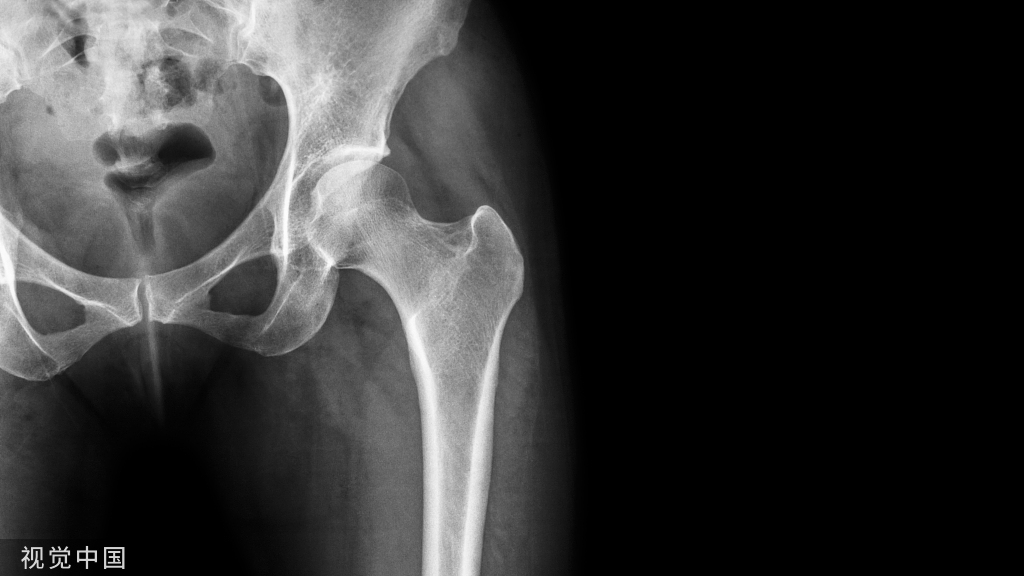

骨质疏松症是一种以骨量减少和骨组织微结构恶化为特征的系统性骨骼疾病,长期骨质流失导致骨强度受损和骨折风险增加,同时易伴发肌少症,多见于绝经后女性和老年男性,可分为原发性和继发性骨质疏松症[1-2]。